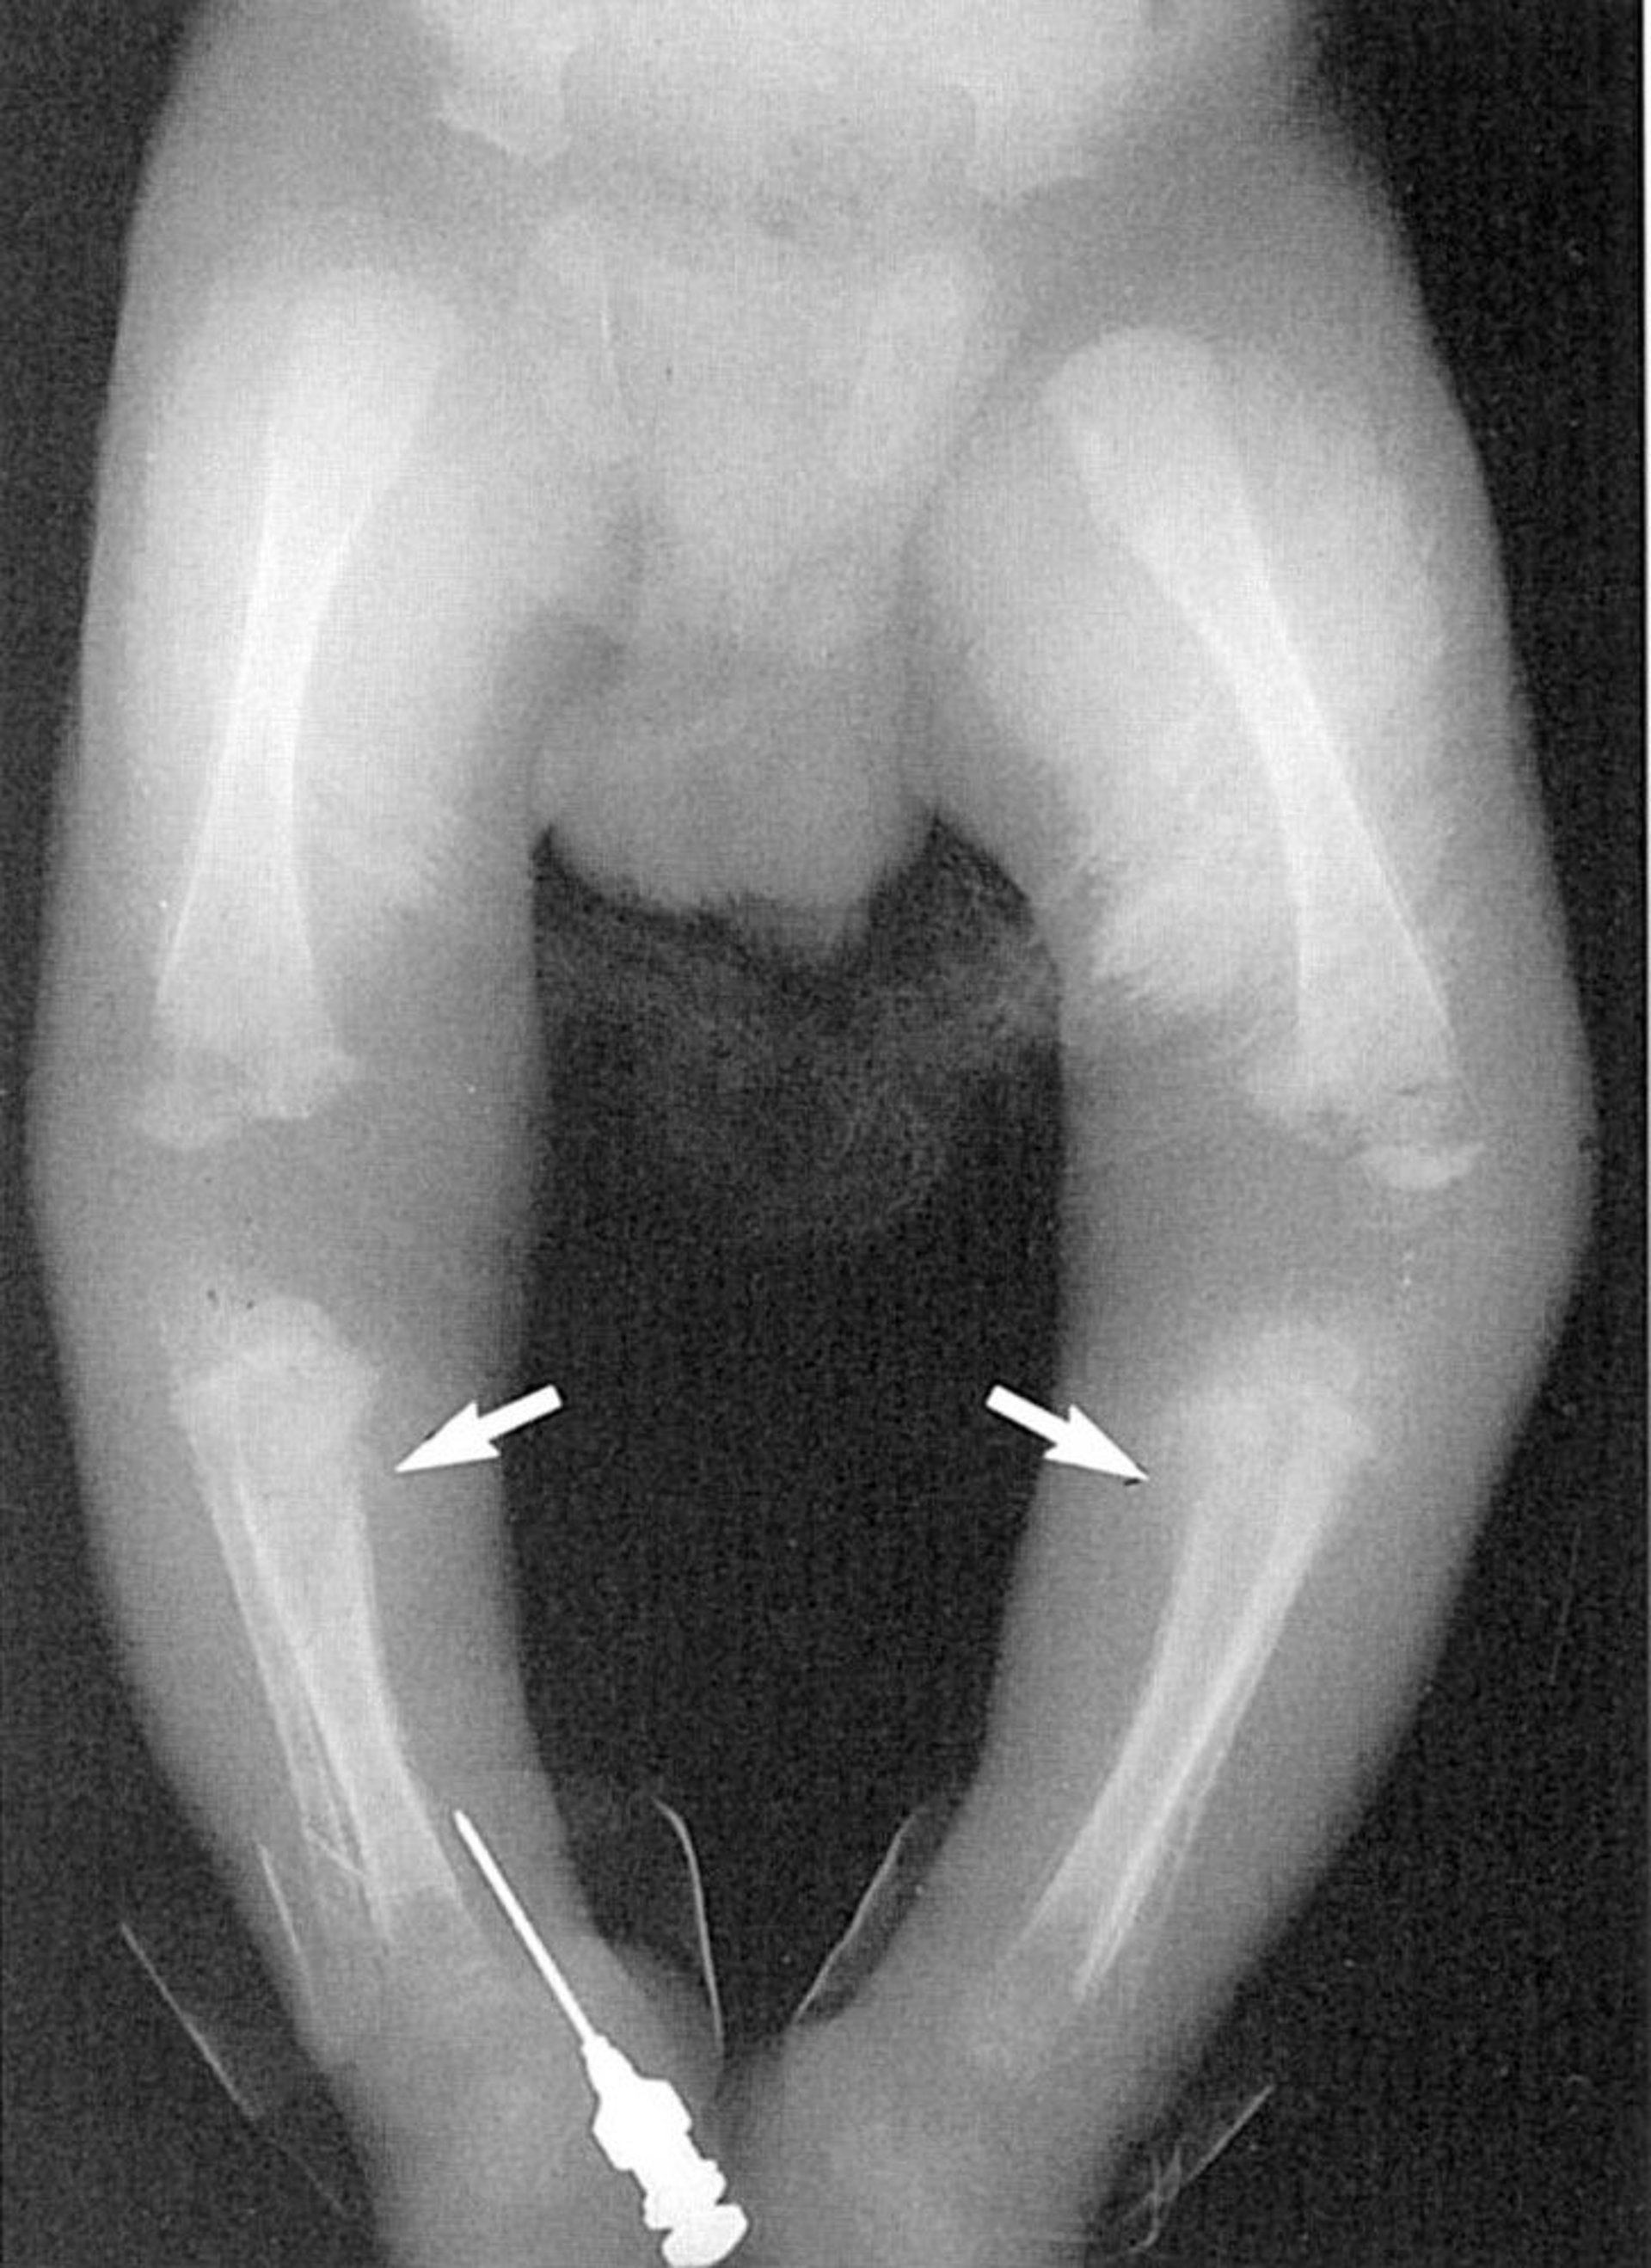

Wimberger Sign

This photo shows lytic lesions in the medial proximal tibia (arrows).